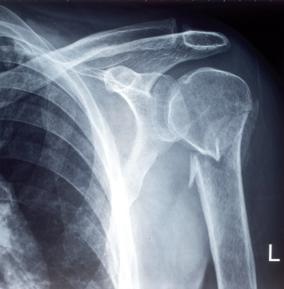

Abb. 7: Benenne die Teile des Skeletts, welche du auf den Röntgenbildern siehst! Schreibe sie auf die Zeilen darunter!

Gib an, welche Verletzungen man mit Hilfe von Röntgenbildern erkennen kann!

Begründe das Aussehen einiger Knochen mit ihrer Funktionsweise!

Röntgenstrahlen können durch unseren Körper dringen und machen unsere Knochen sichtbar. Röntgenbilder werden gemacht, um Verletzungen oder bestimmte Knochenkrankheiten feststellen zu können.